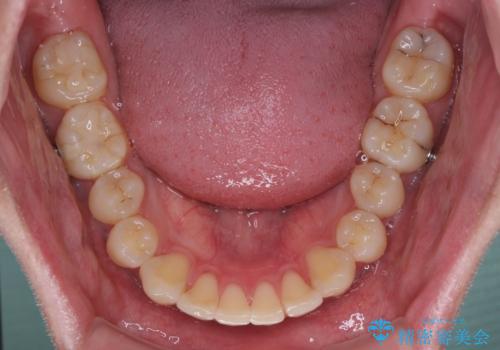

お仕事が忙しく、1日の装着時間は不十分となる日もありましたが、治療は順調に進めていくことができました。

途中、以前大きなむし歯で処置をした歯が痛み出し、根管治療が必要となったため、根管治療とオールセラミッククラウンによる補綴治療を行い、その後にインビザラインによる仕上げの歯列移動を行い、無事に治療を終えることができました。